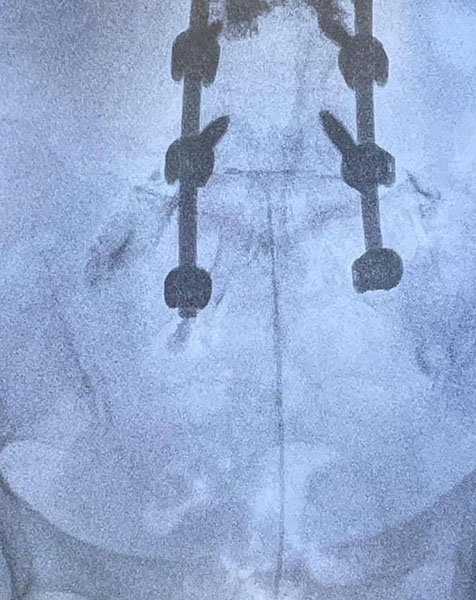

L’epidurolisi è una tecnica mininvasiva che prevede, sotto guida fluoroscopica ed in anestesia locale o blanda sedazione, l’introduzione di un catetere/elettrodo che attraverso una lisi meccanica e farmacologica, permette lo sbrigliamento delle radici nervose riducendo così la sintomatologia dolorosa. È possibile, inoltre, attraverso la punta di questo particolare elettrodo, eseguire la radiofrequenza pulsata gangliare a più livelli.

CASE STUDY EPIDUROLISI